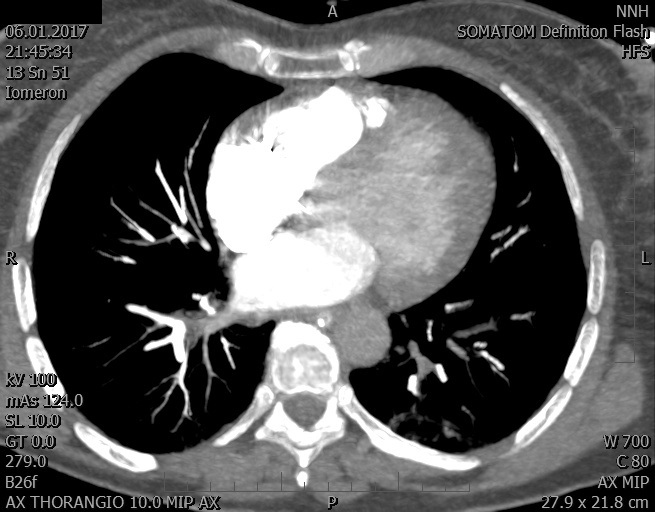

Video 1 - Akutní koronarografie prokázala normální nález na věnčitých tepnách s výjimkou suspekce na lehký spasmus na pravé koronární tepně.Echokardiograficky byla zjištěna těžká dysfunkce dilatované levé komory s nezvětšenou pravou komorou (video 2).

Video 2 - Echokardiograficky byla zjištěna těžká dysfunkce dilatační levé komory s nezvětšenou pravou komorou.Pro nejasnou příčinu zástavy jsme provedli i vyšetření výpočetní tomografií (CT), které vyloučilo plicní embolizaci (série 1 - soubory na konci článku). V den přijetí při přetrvávající oběhové nestabilitě byla nemocná opakovaně defibrilována pro fibrilaci komor se stabilizací rytmu po podání amiodaronu a mesocainu. Dle hemodynamických měření se jednalo o těžký kombinovaný šok. Vstupní laboratorní vyšetření bylo bez větších pozoruhodností. Posléze jsme doplnili anamnézu od příbuzných a zjistili, že pacientka užila do dvou hodin před srdeční zástavou první tabletu amoxicilinu na lehký respirační infekt. Při nevýtěžnosti vstupních vyšetření a nových anamnestických informacích jsme doplnili 14 hodin po kolapsu vyšetření koncentrace tryptázy v séru, která byla extrémně zvýšena (tabulka 2), což nás vedlo k podezření na anafylaxi.